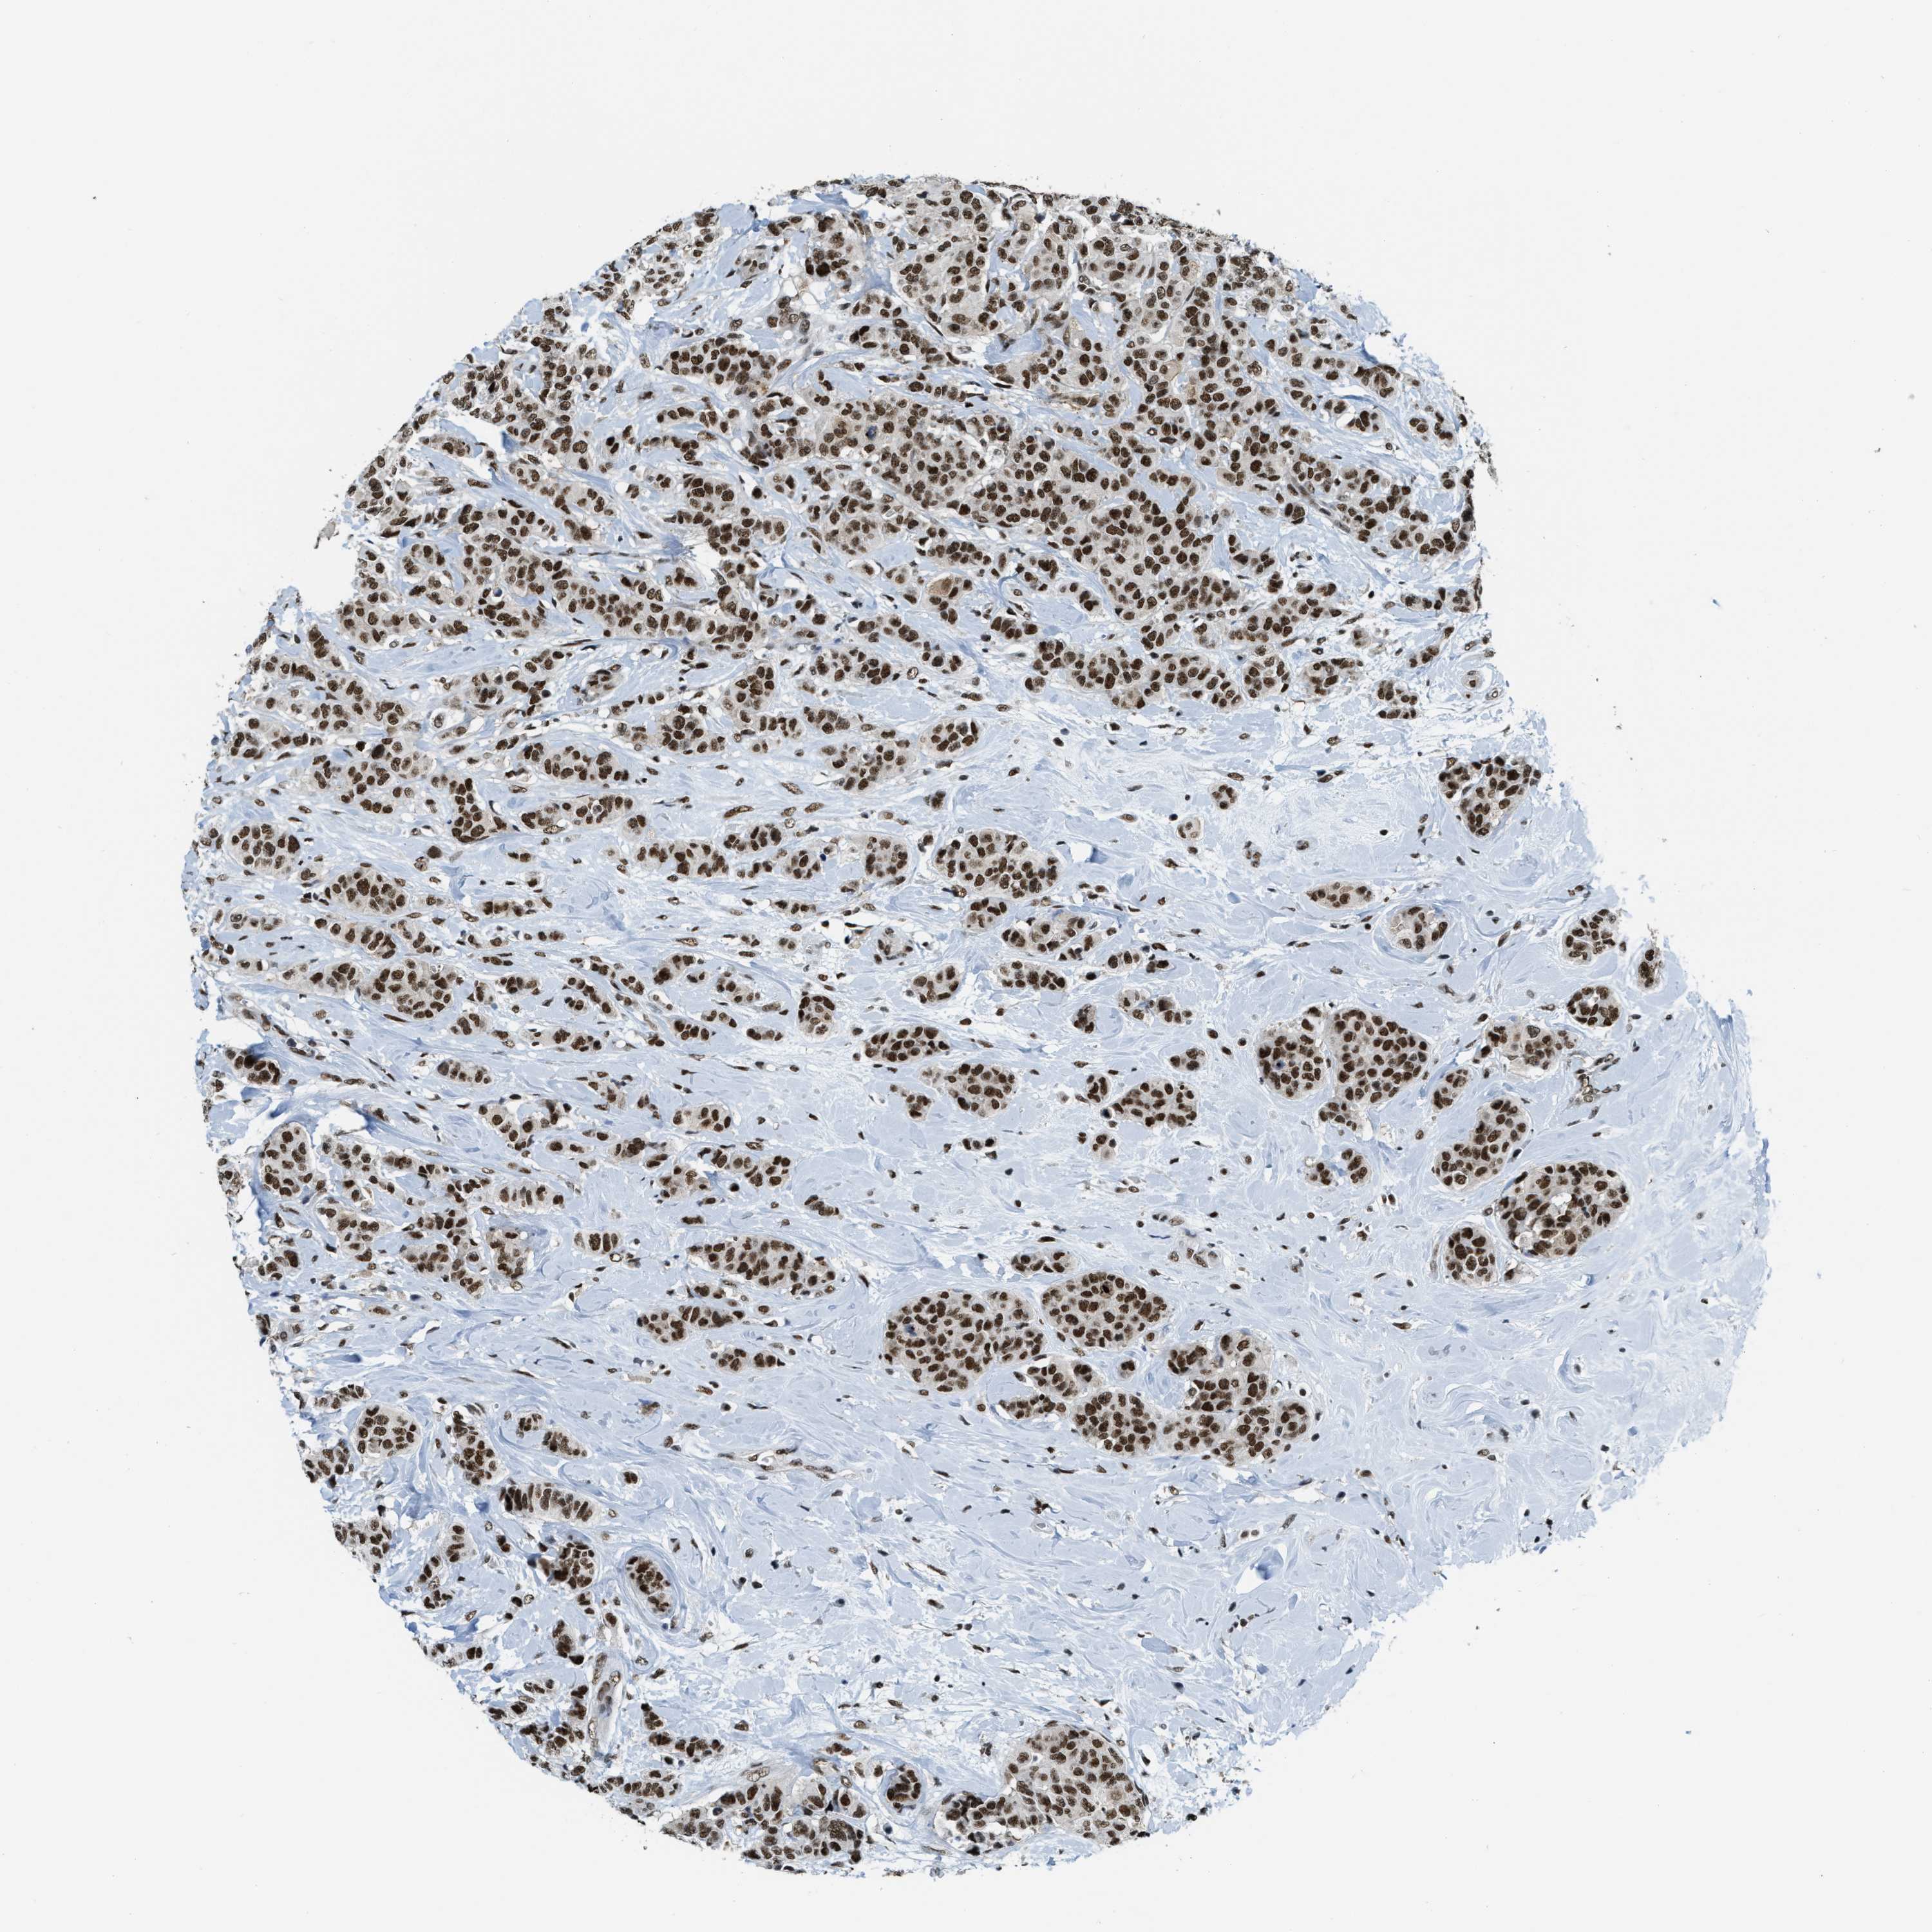

CANCER BREAST CANCER Show tissue menu

BRCA TCGA BRCA VALIDATION PROTEIN EXPRESSION